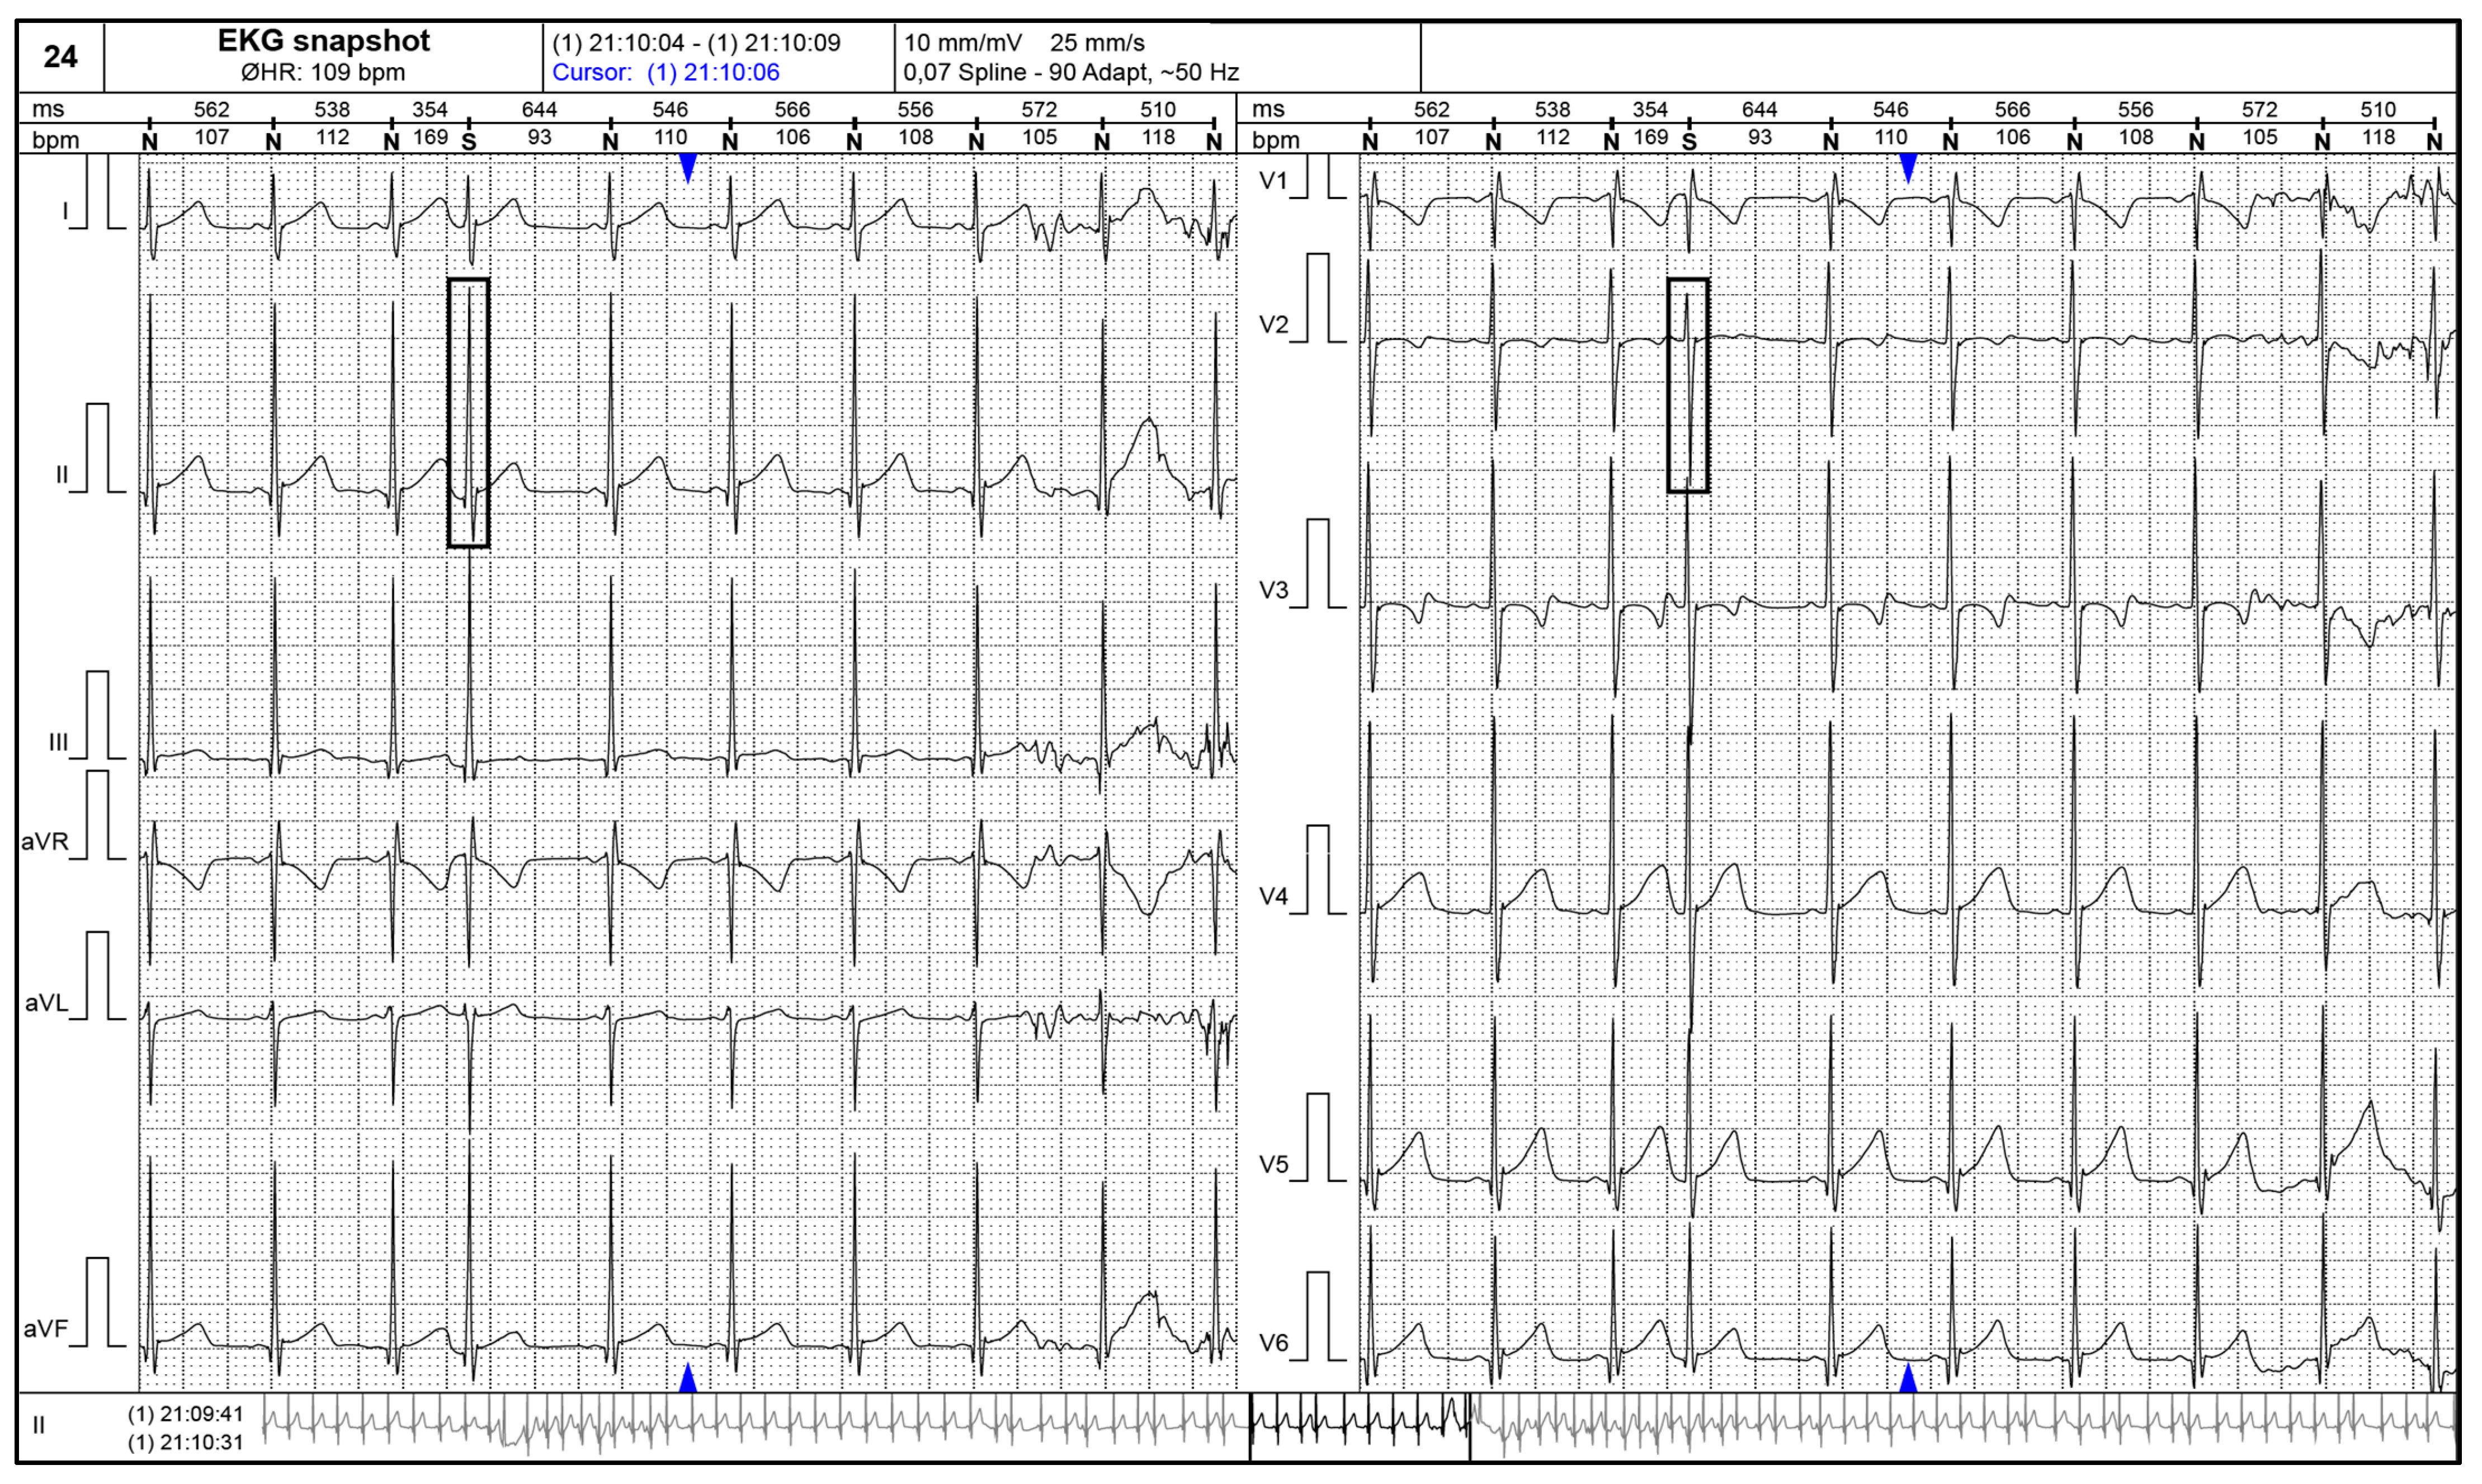

Figure 2 and Figure 3 present supraventricular ectopic beats in a neonate with TS and electrocardiographic changes (short PR interval) in a 2–years–old patient with TS.

Figure 2.

24–h ECG Holter monitoring showing a supraventricular ectopic beat (black rectangular shapes) in a neonate with tuberous sclerosis.